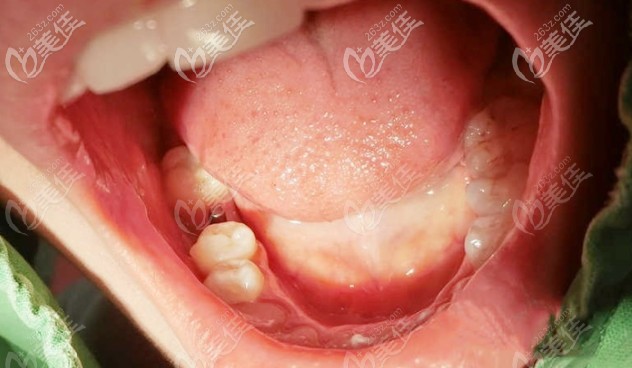

術(shù)后照片:

這是我現(xiàn)在牙齒的樣子,是不是看不出來是種植牙,而且用著還是很滿意的,到目前為止沒有出現(xiàn)任何問題。